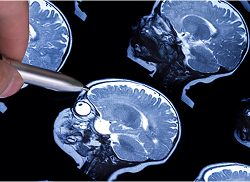

Additionally, hydrocephalus in infants and older children is usually diagnosed in one of three ways: ultrasound, computed tomography (CT scan), and magnetic resonance imaging (MRI).

Magnetic resonance imaging combines large magnets and radio waves to show detailed images of organs inside a baby’s body.